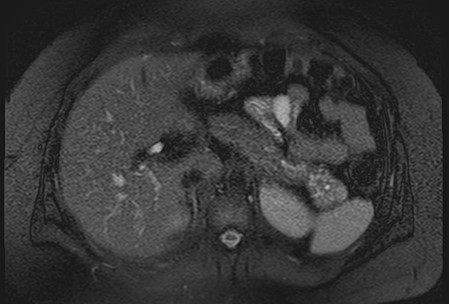

Paciente femenina de 48 años de edad que ingresa a Hospital Sanatorio Franchin por síntomas de cefalea y mareos, cuadro que se hace progresivo, presentando síncopes y posteriormente alteración del estado de conciencia. Los exámenes clínicos revelan una glucosa de 40 mg/dl, concomitante con insulina alta y péptido C elevado. Ingresa de forma programada para realización de duodeno pancreatectomía el 29 de mayo de 2021. Imágenes diagnósticas muestran estudio trifásico de tomografía de abdomen, lesión nodular en la cabeza del páncreas con ávido realce en fase arterial que en resonancia magnética se observa hiperintensa en T2, presenta restricción con la difusión y caída de la señal en el ADC. Además presenta realce tras la administración de contraste con gadolinio.

Mujer de 36 años que ingresa a Hospital Sanatorio Franchin el 11 de octubre de 2023 de forma programada para realización de duodeno pancreatectomía cefálica por tumor de cabeza de páncreas en estudio. Refiere hallazgo de lesión en forma incidental durante estudio de control hace dos meses por presentar antecedentes familiares (neoplasia endocrina múltiple). Se interna para manejo quirúrgico. Estudios de tomografía revelan formación nodular localizada en cabeza y cuerpo pancreático de paredes gruesas que mide 24 x 28 mm, que en resonancia se muestra hiperintensa en T2 y realce periférico luego de la administración de contraste endovenoso. Presenta restricción en la difusión con caída de la señal ADC, por lo que se vincula con una lesión de alta celularidad.

La resonancia magnética es el otro estudio de imagen no invasivo que nos permite la detección de la lesión con una sensibilidad mayor que la de la tomografía, del 85% al 95%, donde los insulinomas presentan un realce tras la administración de contraste con gadolinio y secuencias T1 sin contraste son lesiones hipointensas y en secuencias T2 son hiperintensas.

La resonancia magnética confirmó aún más el diagnóstico de las lesiones ya previamente visualizadas en tomografía en esta revisión, con realce de las lesiones en secuencias T1 y contraste con gadolinio, y en las secuencias funcionales con restricción de la lesión y caída de la señal en el mapa de ADC.